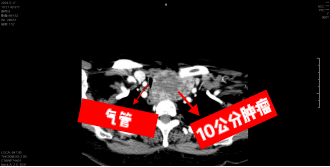

患者颈部增强CT提示:1.胸骨后甲状腺肿,下界达主动脉弓以下。2.气管明显受压右偏,最窄处直径仅约3mm。综合相关检查结果,患者诊断明确,考虑:1.左侧胸骨后甲状腺肿;2.右侧甲状腺乳头状癌。患者胸骨后肿瘤较大,足足有10公分以上,并且已经压迫到气管,导致气管严重狭窄,需要及时手术,否则将会有因呼吸困难导致窒息的风险。因患者肿瘤较大,颈部毗邻结构复杂,手术空间很小,术中还会有开胸的可能,且右侧甲状腺考虑乳头状癌,亦需要手术处理,手术难度大且风险高。同时患者气管狭窄明显,麻醉气管插管难度大,且术后拔管后有气管塌陷窒息风险。